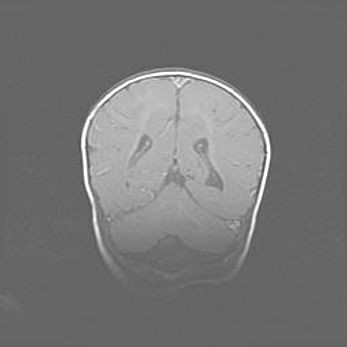

Наружная гидроцефалия с возможной атрофией височных областей.

Возраст: 28 дней

Вес: 3670 г

Пол: мужской

Окружность головы: 38 см

Срок гестации: 40 недель

Гидроцефалия головного мозга у новорожденных – это заболевание, которое характеризуется скоплением избыточного количества спинномозговой жидкости в желудочковой системе головного мозга в результате затруднения её перемещения от места выработки к месту поглощения в кровеносную систему или вследствие нарушения абсорбции. При открытой наружной форме гидроцефалии у новорожденных расширяются и переполняются субарахноидные пространства.

При нормотензивных  формах,  которые,  как  правило,  являются  следствием  перенесенных ишемических  повреждений  паренхимы  мозга,  возможно  сочетание микроцефалии  с нормотензивной гидроцефалией. В основе данных изменений лежит атрофия больших полушарий с преимущественной  локализацией  в  лобно-височных  областях.